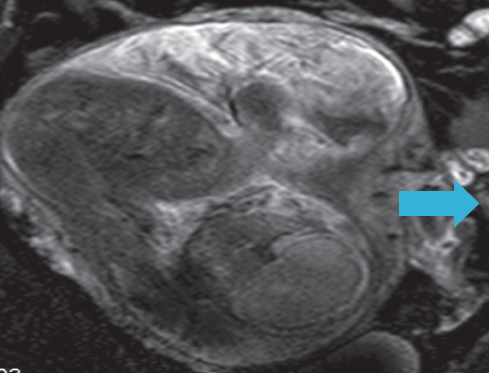

James Gendernalik, DO; Michael Flicker, MD

A 38-year-old woman, who was 28 weeks pregnant, presented with a 2-day history of worsening left lower quadrant abdominal pain.